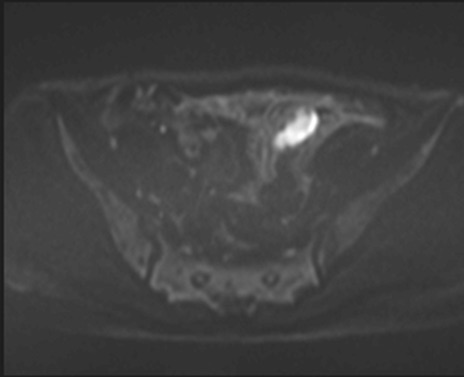

症例39 DWI/ADC

MRI(4日後)